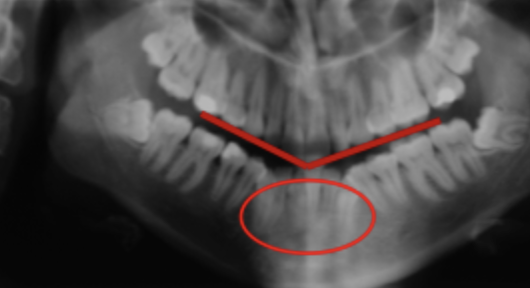

Patient position - Air shadow

Failure to instruct patient to press tongue to roof of mouth.